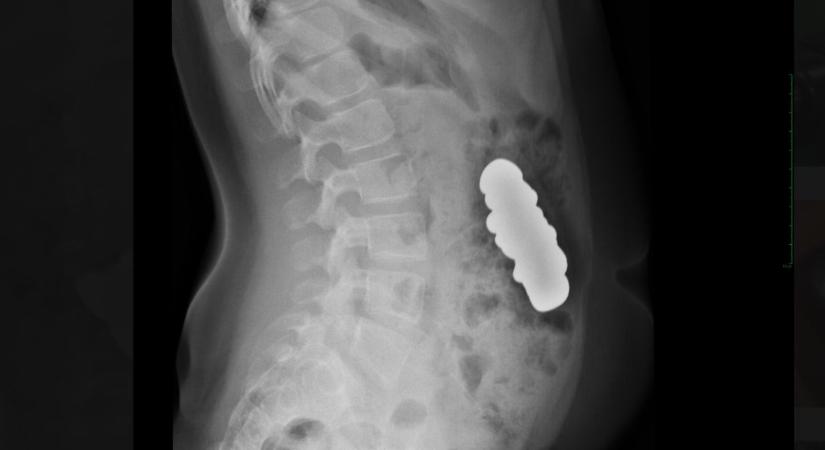

Húsz mágnest nyelt le egy gyerek

Budapesten operálták meg.